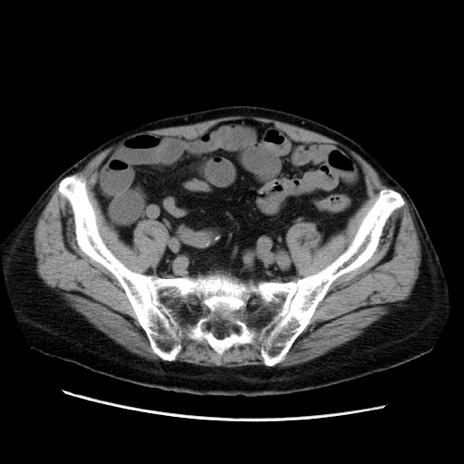

症例21(横断像)

【症例】70歳代男性

【主訴】腹痛

【現病歴】肝硬変・肝細胞癌にてかかりつけの方。約9時間前に食後より腹痛出現。症状が徐々に増悪し、嘔吐出現したため来院。

【既往歴】肝硬変、肝細胞癌(RFA、TACE後)

【身体所見】意識清明、表情苦悶様、BT 36℃、BP 129/78mmHg、P 88bpm、SpO2 97%(RA)、右上腹部から心窩部にかけて圧痛あり、反跳痛なし、筋性防御あり。

【データ】WBC 5800、CRP 0.16